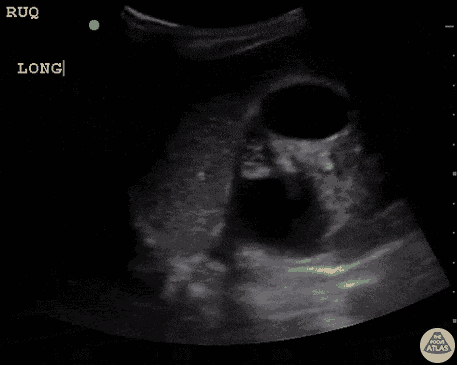

Renal/GU - Severe Hydronephrosis in Prune Belly Syndrome

10 y/o with Prune Belly Syndrome presenting with suprapubic pain. Bilateral severe grade IV hydronephrosis. Bear claw appearance of left kidney. Prune Belly Syndrome is a rare disorder known for lack of abdominal muscles, cryptorchidism, and urinary tract malformations. Dr. Sathya Subramaniam, Pediatric EM Fellow - Kings County/SUNY Downstate